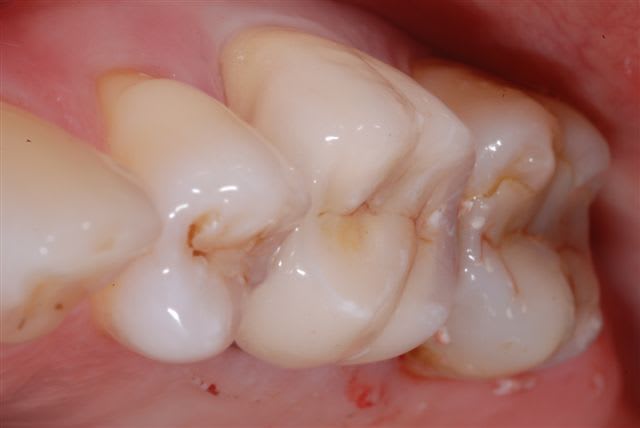

07/02/2010 à 23h27

certes j'aurais pu enlever la totalité du ciment avant de prendre la photo.

ça à l'air plutôt bien, non?

c'est quand meme beaucoup moins important d'avoir la perfection esthétique au niveau d'une 6

le pire c'est l'incisive centrale sup(quand il n'y en a qu'une à faire)